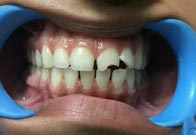

(6) Teeth Whitening

Before Treatment

After Treatment

Patient reported to us with the concern of Yellow teeth. Patient was conscious in social gatherings due to lack of confidence. Complete gum treatment and polishing was done for the patient followed by in office bleaching to achieve 2 shade whiter teeth. Home kit was a also delivered to the patient for maintenance as patient was coming from far.